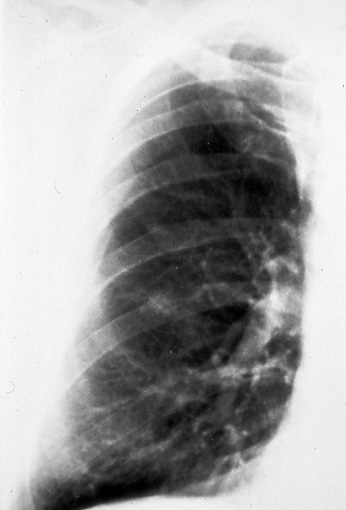

Fig.

6a: Posterior-anterior

chest radiograph shows

a T1 (<3 cm) peripheral

cancer in the right lower

lobe. This lesion is seen

to better advantage on

a conventional tomogram,

Fig. 6b. Note the spiculated,

irregular margins. |